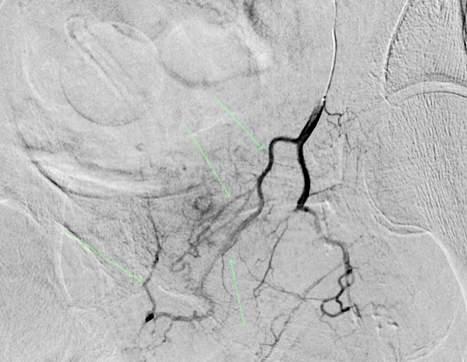

Issuu converts static files into: digital portfolios, online yearbooks, online catalogs, digital photo albums and more. Sign up and create your flipbook.